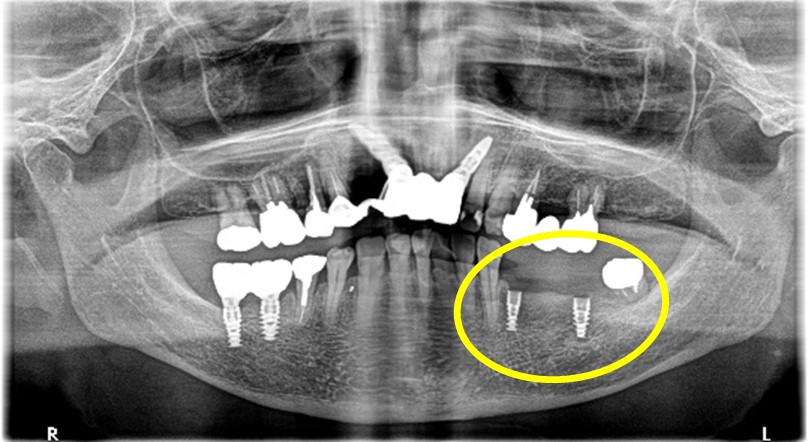

Before

After